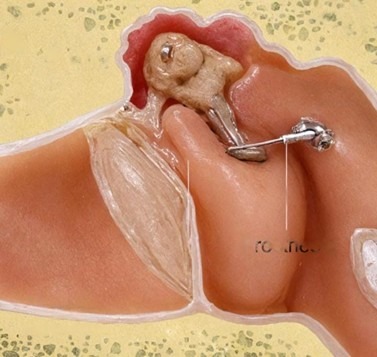

At Richardsons Face Hospitals, we offer the best ENT treatment in India as it is the surgery that is done to treat hearing loss or hearing impairment by removing a dysfunctional small piece of bone known as the stapes, aka stirrup, and replacing the bone with a small piston in the ear. This condition is known as otosclerosis, in which there is abnormal bone remodeling that causes the stapes bone to become unable to vibrate normally, and in turn impairing hearing. This occurs because the stapes bone becomes abnormally fused to the surrounding structures and hinders its vibration. For the best ENT treatment in India, this surgery provides a permanent solution to restore hearing and improve quality of life.

The surgery involves removing the abnormal, dysfunctional bone and replacing it with a small prosthesis made up of Teflon, nitinol, or titanium (varies from patient to patient and availability). When you get the best ENT treatment in India from us, we assure you the permanent cure. This piston now acts in the place of the stirrup and vibrates, permitting sound waves to reach the inner ear and restore hearing. For the Best ENT Treatment in India, this surgery is a highly effective and permanent solution.